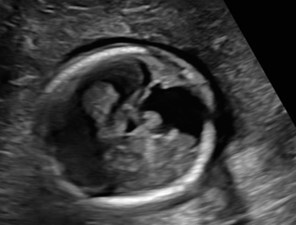

A 24-year-old gravida 1 with a dichorionic-diamniotic twin pregnancy at 16w1d gestation was evaluated by Maternal-Fetal Medicine who identified multiple possible cranio-facial abnormalities in Twin A on transabdominal ultrasound. This raised the concern for a possible chromosomal abnormality as well as holoprosencephaly as the cavum septum pellucidum was not visualized. A detailed transabdominal ultrasound performed at 16w1d provided the initial assessment of the abnormal-appearing left cerebrum of Twin A (Figure 1). The left cerebral ventricle was overall poorly visualized, however, the posterior aspect of the left ventricle appeared to be significantly more dilated compared to the normal-appearing right ventricle. The cavum septum pellucidum could not be visualized, the thalami appeared fused, and the temporal areas of the facies appeared more angulated than expected. The patient was scheduled for a fetal MRI which was performed at 19w1d gestation and showed complete architectural distortion involving the left cerebral hemisphere of Twin A, with a mass-like structure measuring approximately 2.4 x 2.3 x 1.8 cm, along with a loss of normal gray-white differentiation (Figure 2). The diagnoses based on this MRI were either a neoplastic growth or a migrational anomaly.